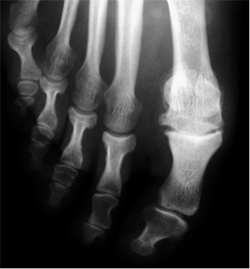

Es una limitación de la movilidad de la articulación metatarsofalángica del dedo gordo. Esta limitación altera el funcionamiento normal del pie y puede producir dolor. Cuando progresa, aparece una prominencia dorsal en esta articulación que puede ser muy dolorosa.

Hay muchos tipos de cirugía para tratar el hallux rígidus. Cada especialista tiene sus preferencias en función de su formación y experiencia. El hallux rígidus puede tener diferentes grados evolución. Dependiendo del grado evolutivo puede ser necesario: resección protuberancia, osteotomías (cortes) de los huesos o fijación de la articulación.